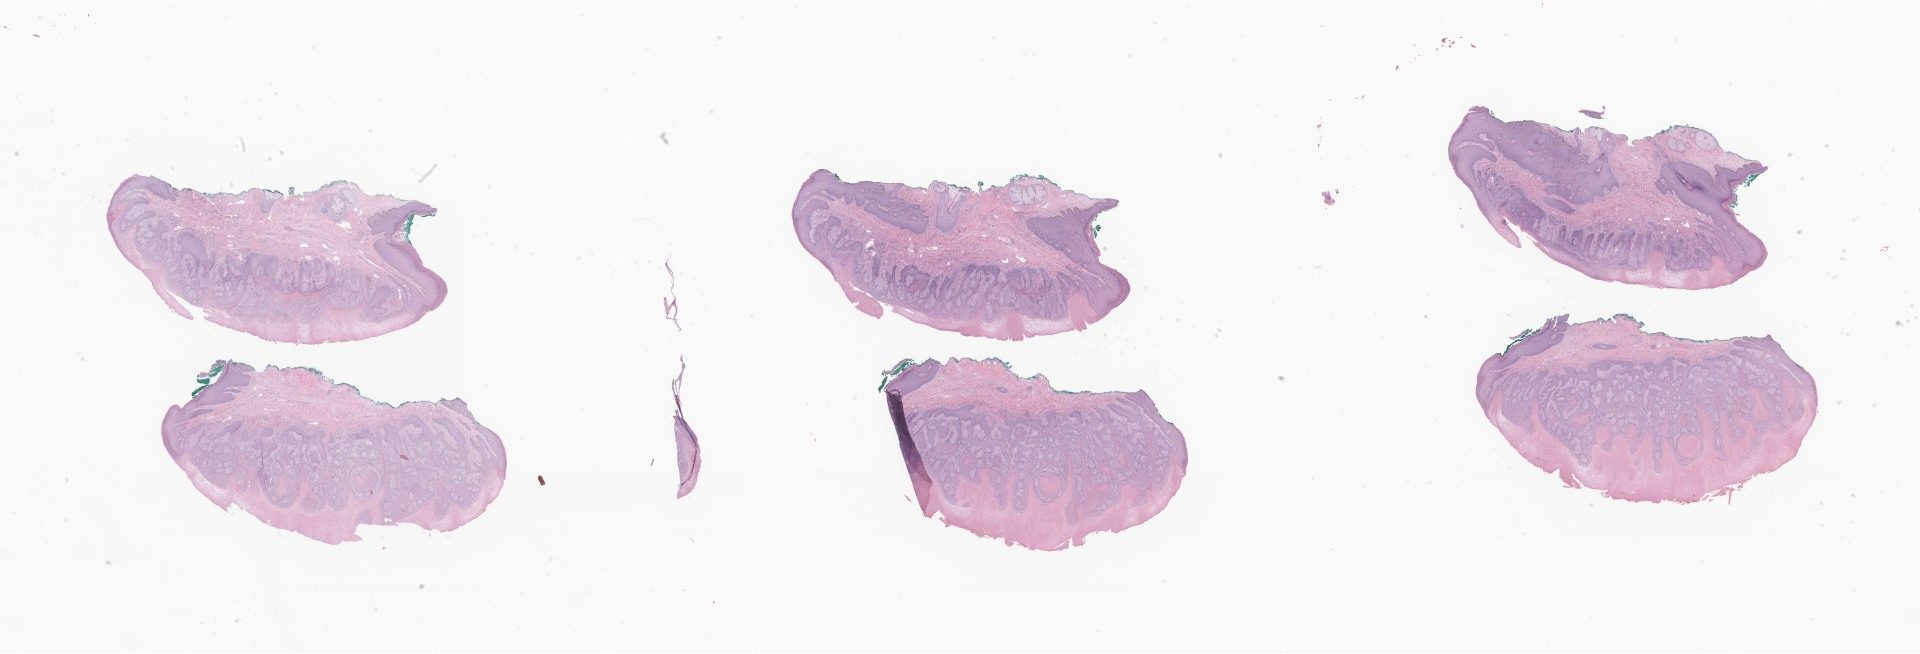

HE.svs

134853

x

45923

@

40X